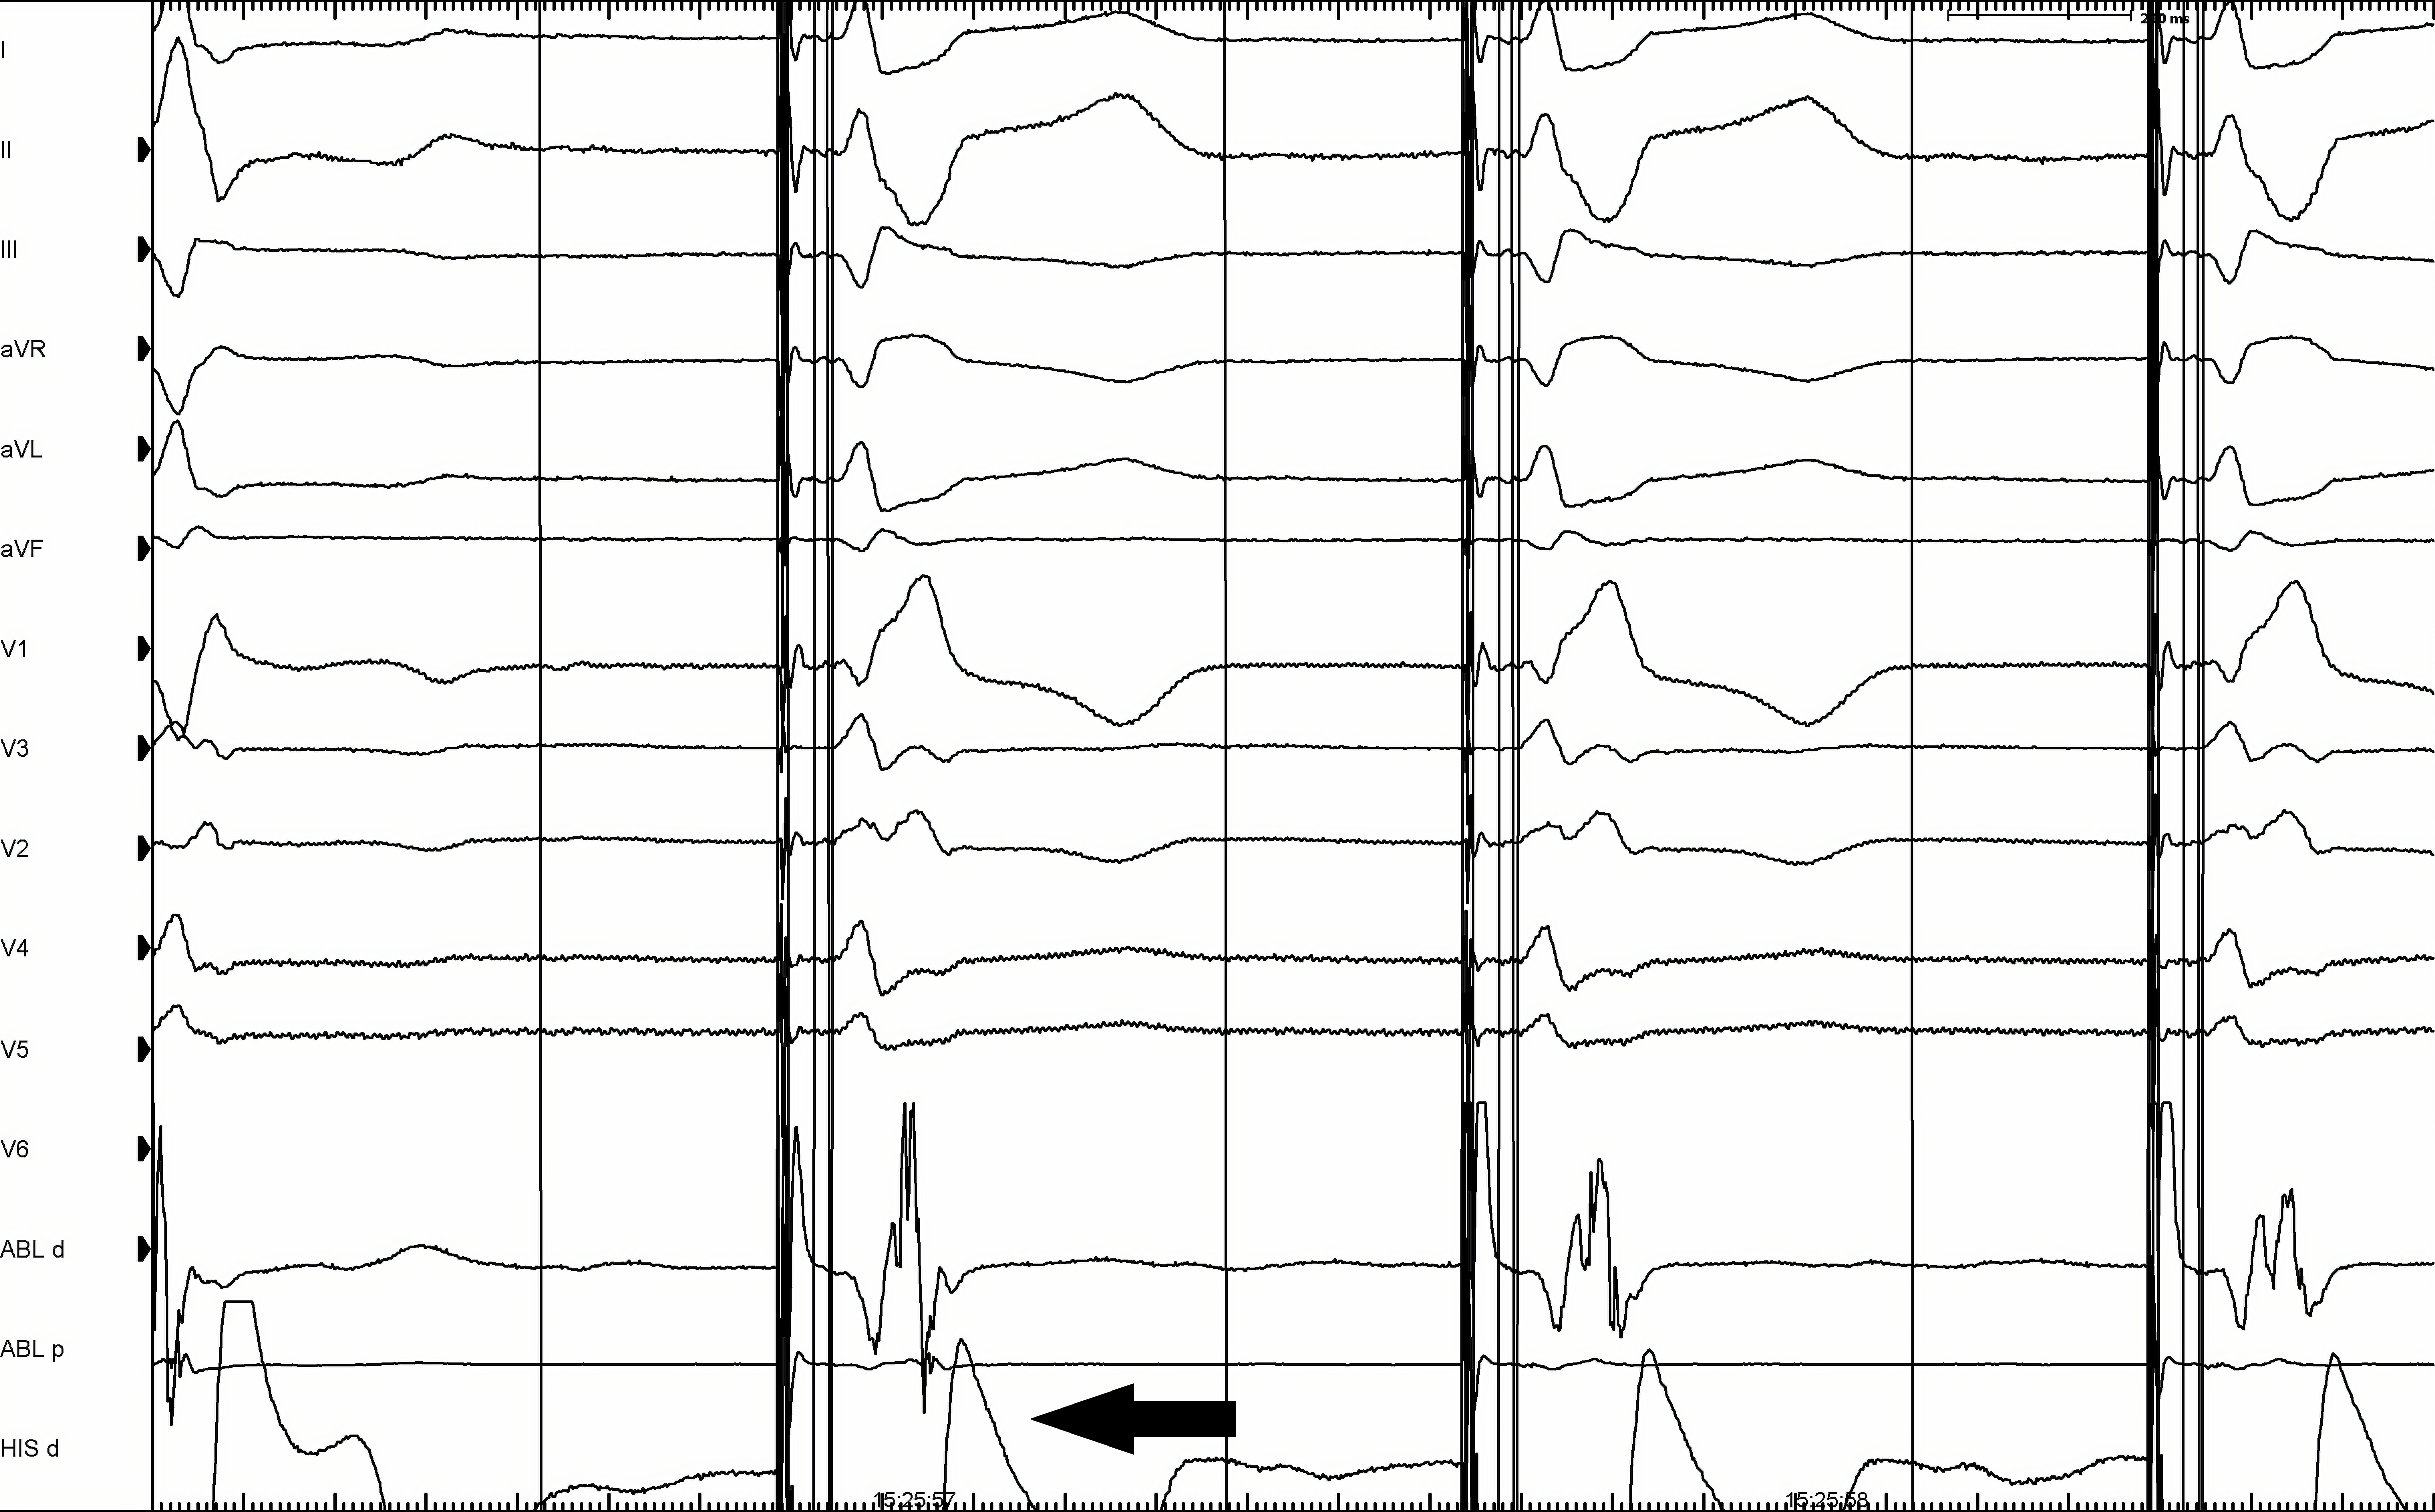

- Обычно определяется один порог стимуляции (С-СПГ), но у пациентов с нарушением проведения по системе Гиса-Пуркинье будет определяться 2 значения порога стимуляции — с и без коррекции нарушения проведения. На рисунке 2 изображен пример С-СПГ в сочетании с блокадой правой ножки ПГ.

Рис. 2. С-СПГ.

Примечание: пример достигнутой С-СПГ с интраоперационно развившейся блокадой правой ножки пучка Гиса. Черная стрелка указывает на дискретный желудочковый сигнал, полученный с электрода в гисиальной позиции. Скорость записи 100 мм/сек.